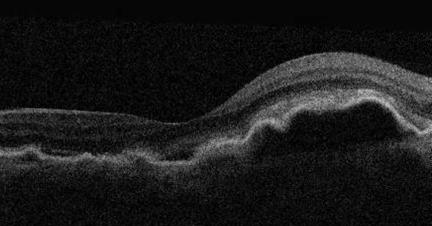

Kosteassa silmänpohjarappeumassa puolestaan verkokalvokerrosten alle alkaa kasvamaan hauraita verisuonia, jotka tihkuvat verta ja nesteitä. Kostea silmänpohjarappeuma kehittyy yleensä nopeasti ja aiheuttaa näkökentässä suorien viivojen yht’äkkistä vääristymistä sekä osassa tapauksissa myös keskeisessä näkökentässä läiskämäisiä puutosalueita. Kostea silmänpohjarappeuma vaatii aina silmätautienerikoislääkärin tarkempaa tutkimusta ja hoitoa. Yleisin tähän Suomessa käytetty hoitomuoto on lasiaistilaan annosteltavat verisuonikasvutekijöiden estäjät, jotka vähentävät nestettä tihkuvien uudissuonten muodostumista.

Nestekertymää silmänpohjan verkkokalvokerrosten alla